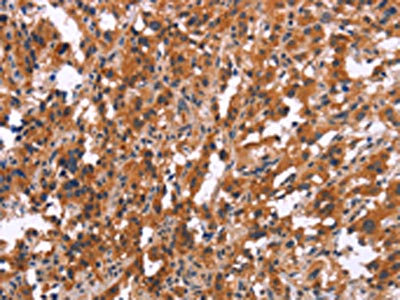

The image on the left is immunohistochemistry of paraffin-embedded Human thyroid cancer tissue using CSB-PA928010(MAPK11 Antibody) at dilution 1/15, on the right is treated with synthetic peptide. (Original magnification: ×200)

The image on the left is immunohistochemistry of paraffin-embedded Human tonsil tissue using CSB-PA928010(MAPK11 Antibody) at dilution 1/15, on the right is treated with synthetic peptide. (Original magnification: ×200)